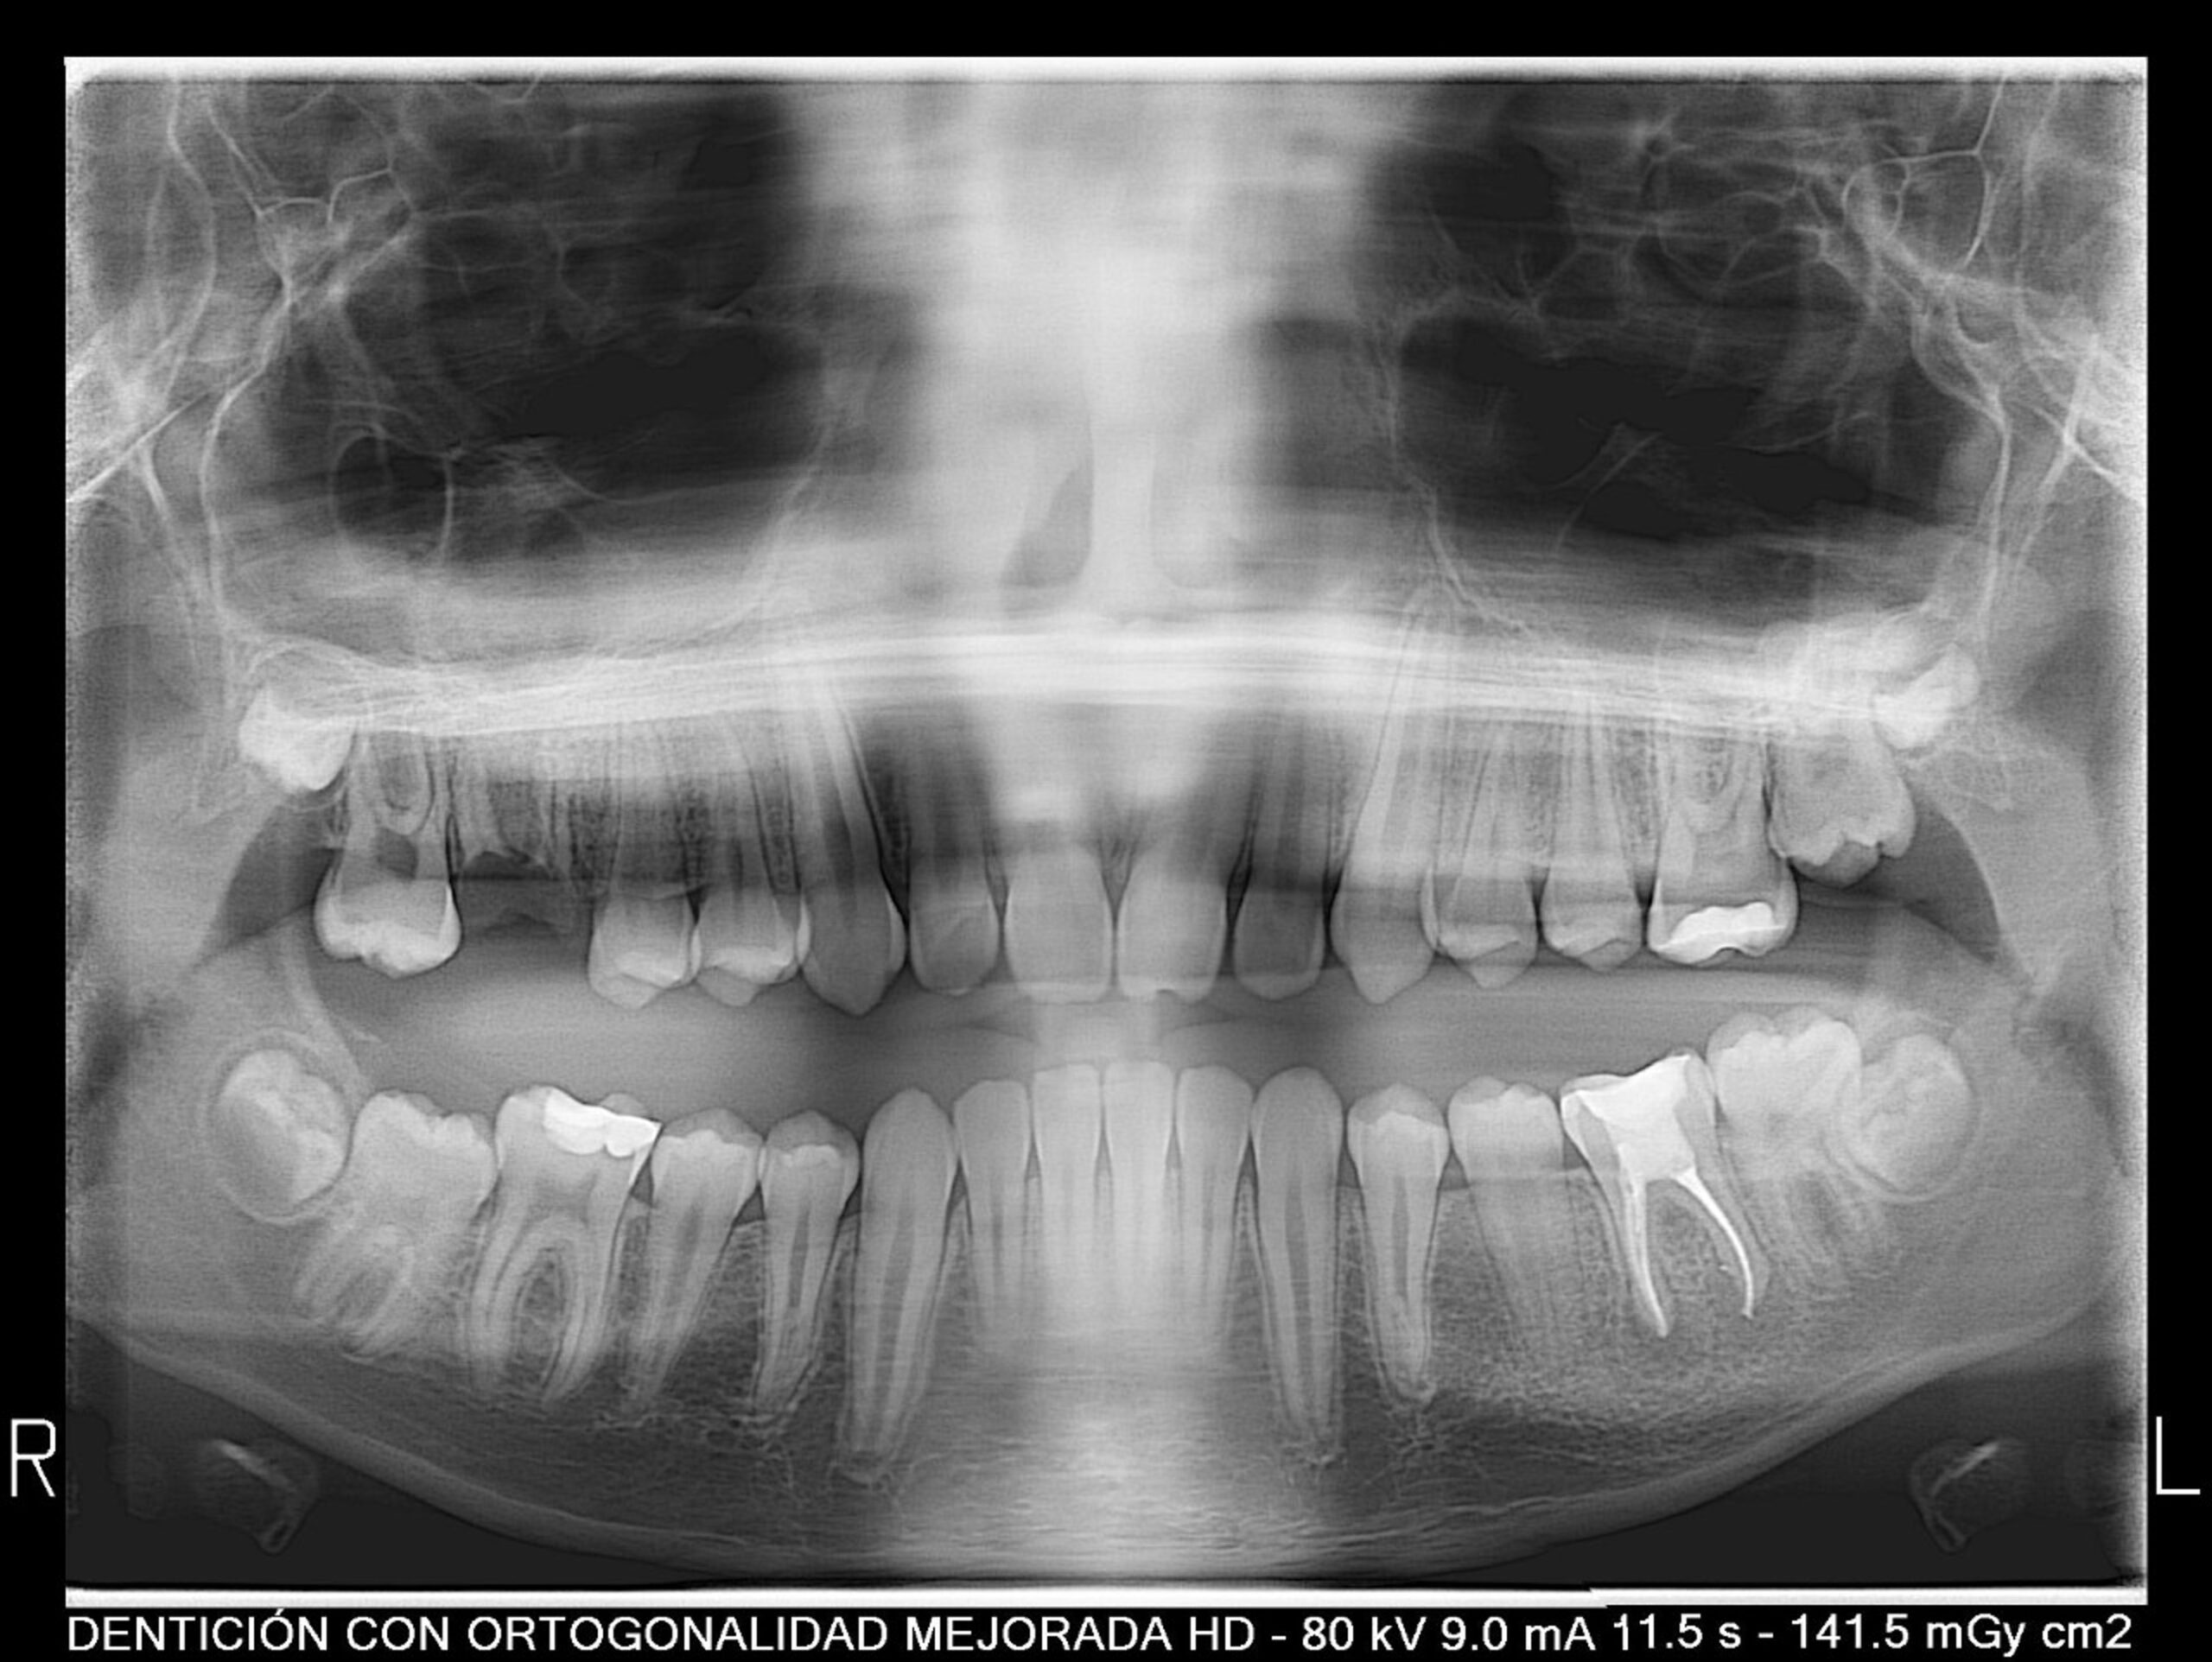

Nos encontramos con un caso en un timming adecuado para realizar un avance mandibular. También, nos favorece la inclinación el ángulo goniaco de 123 grados y la motivación del paciente. En contra nos perjudica la inclinación del incisivo inferior de 100 grados (lo podríamos controlar con microimplantes en la meseta inferior o alineadores, pero el paciente rechaza ambas opciones). Por otra parte,  en la radiografía frontal observamos un resto radicular en el 16, que decidimos extraer, y a petición del paciente, cerrar el espacio con mesialización del 17.

CLASE II MOLAR Y CANINA BILATERAL CON PERFIL DE MANDÍBULA RETRUSIVA AVANCE MANDIBULAR (CAMBIOS A NIVEL FACIAL+ CLASE I MOLAR Y CANINA)

RESTO RADICULAR DE 16 EXTRACIÓN DEL 16 Y MESIALIZACIÓN DE 17

(USAR MICROTORNILLO DE ANCLAJE INDERECTO 15)